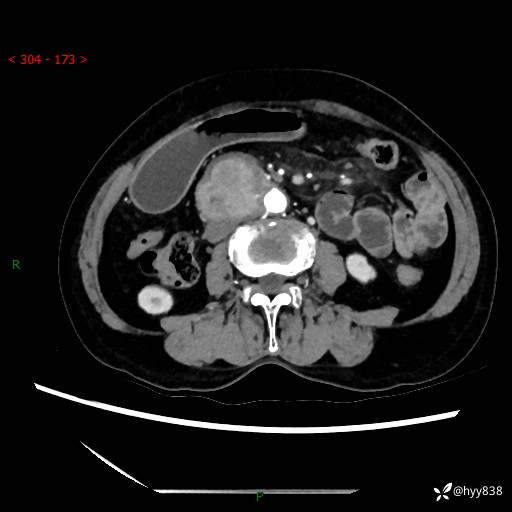

71岁/女,腹痛1月余。腹膜后肿物,间质瘤 VS 副节瘤 VS 平滑肌肉瘤---(有结果)

【患者信息】:71岁/女

【主诉】:腹痛1月余

【现病史及既往史】:患者于1月前无明显诱因出现右下腹部疼痛不适,呈阵发性隐痛,尚可耐受,放射至后背部及腰部疼痛,伴排便困难,不伴其它部位疼痛,无嗳气,无不洁饮食,无黑便,无恶心、呕吐、腹胀腹泻、呕血、发热、寒颤、厌油、黄疸,多次就诊于当地区太湖医院拍片示: 行抗炎等对症支持治疗,效果尚可。现患者上述不适症状明显进一步加重,为求进一步治疗遂来我院门诊就诊,门诊以“十二指肠肿瘤?”收住我科。 起病以来,精神、睡眠可,食欲可,大便异常、小便正常,体力、体重无明显下降。

【检查】:腹部CT增强扫描(外院CT平扫)